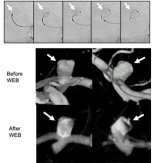

• Sequential images of aneurysm

Figure 6. Intrasaccular flow disruption of an ICA terminus aneurysm using the WEB device. Top panel demonstrates sequential images from left to right showing deployment and finally detachment of the WEB device

Intrasaccular flow disruption: This technique involves placement of a special braided mesh device (for example, the WEB device) inside the aneurysm in order to block blood flow into the aneurysm.  This technique is especially good for aneurysms located at branch points in the vessel, so called bifurcation aneurysms (Figure 6).